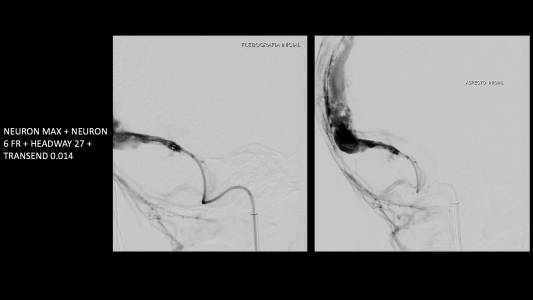

Foi realizada discussão entre as diversas especialidades, em vista da não melhora com o uso do anticoagulante, foi sugerido a tentativa de trombectomia mecânica do seio dural.

O caso clínico apresenta a utilização de materiais com finalidades primárias para trombectomia mecânica no contexto de acidente vascular cerebral (Rebar 27 + Solitaire) e o balão Copernic RC (Balt) comumente utilizado auxiliando na embolização de fístulas durais para os seios, auxiliando no processo de trombectomia mecânica no contexto de extensa trombose venosa cerebral.